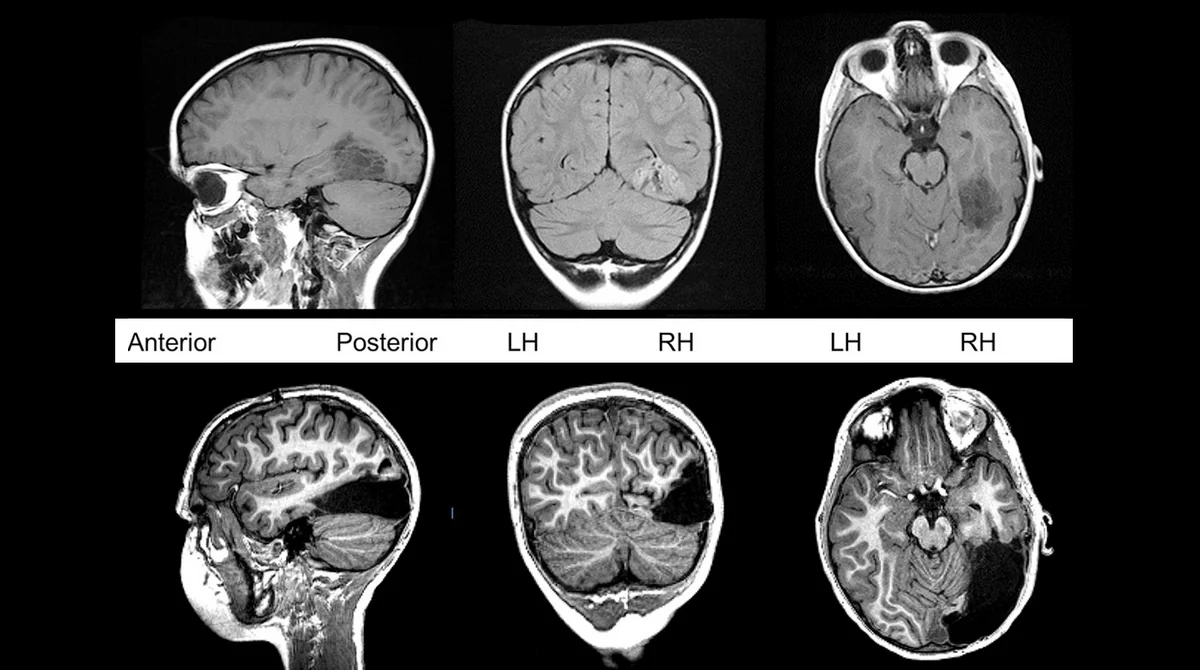

Американские исследователи обнаружили новый тип шизофрении.

Так, у человека с обычной шизофренией наблюдается меньше мозговой ткани, чем у здорового человека. Новый же тип не влияет на объемы серого вещества, они остаются схожими с нормальным мозгом.

Заключение было сделано на основе анализа мозга у 300 пациентов с данным заболеванием.

Профессор радиологии Уоллеса Т. Миллера в Медицинской школе Перельмана в Университете Пенсильвании Кристос Даватцикос заявил, что теперь врачи будут разделять диагноз "шизофрения" на "подтип" и "патологический паттерн" заболевания.